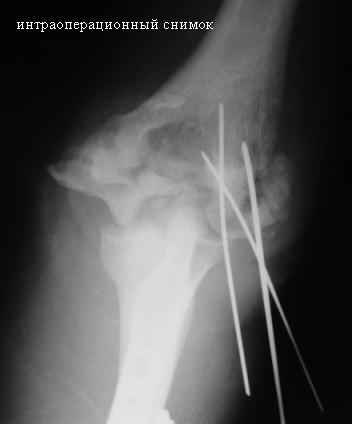

[Ortho] Стойкая комбинированная контрактура правого локтевого сустава

На консультации больной со стойкой комбинированной контрактурой правого локтевого сустава. В прошлом - спортсмен, сейчас охранник. Травма 2 августа 2008г., автодорожная. Оперирован в одной из больниц города. Остеосинтез, два месяца гипс. Объем движений с тех пор не изменился. Боли после физнагрузки (пытается тренироваться).

Хотелось-бы услышать мнения по объему оперативного лечения и послеоперационной реабилитации.